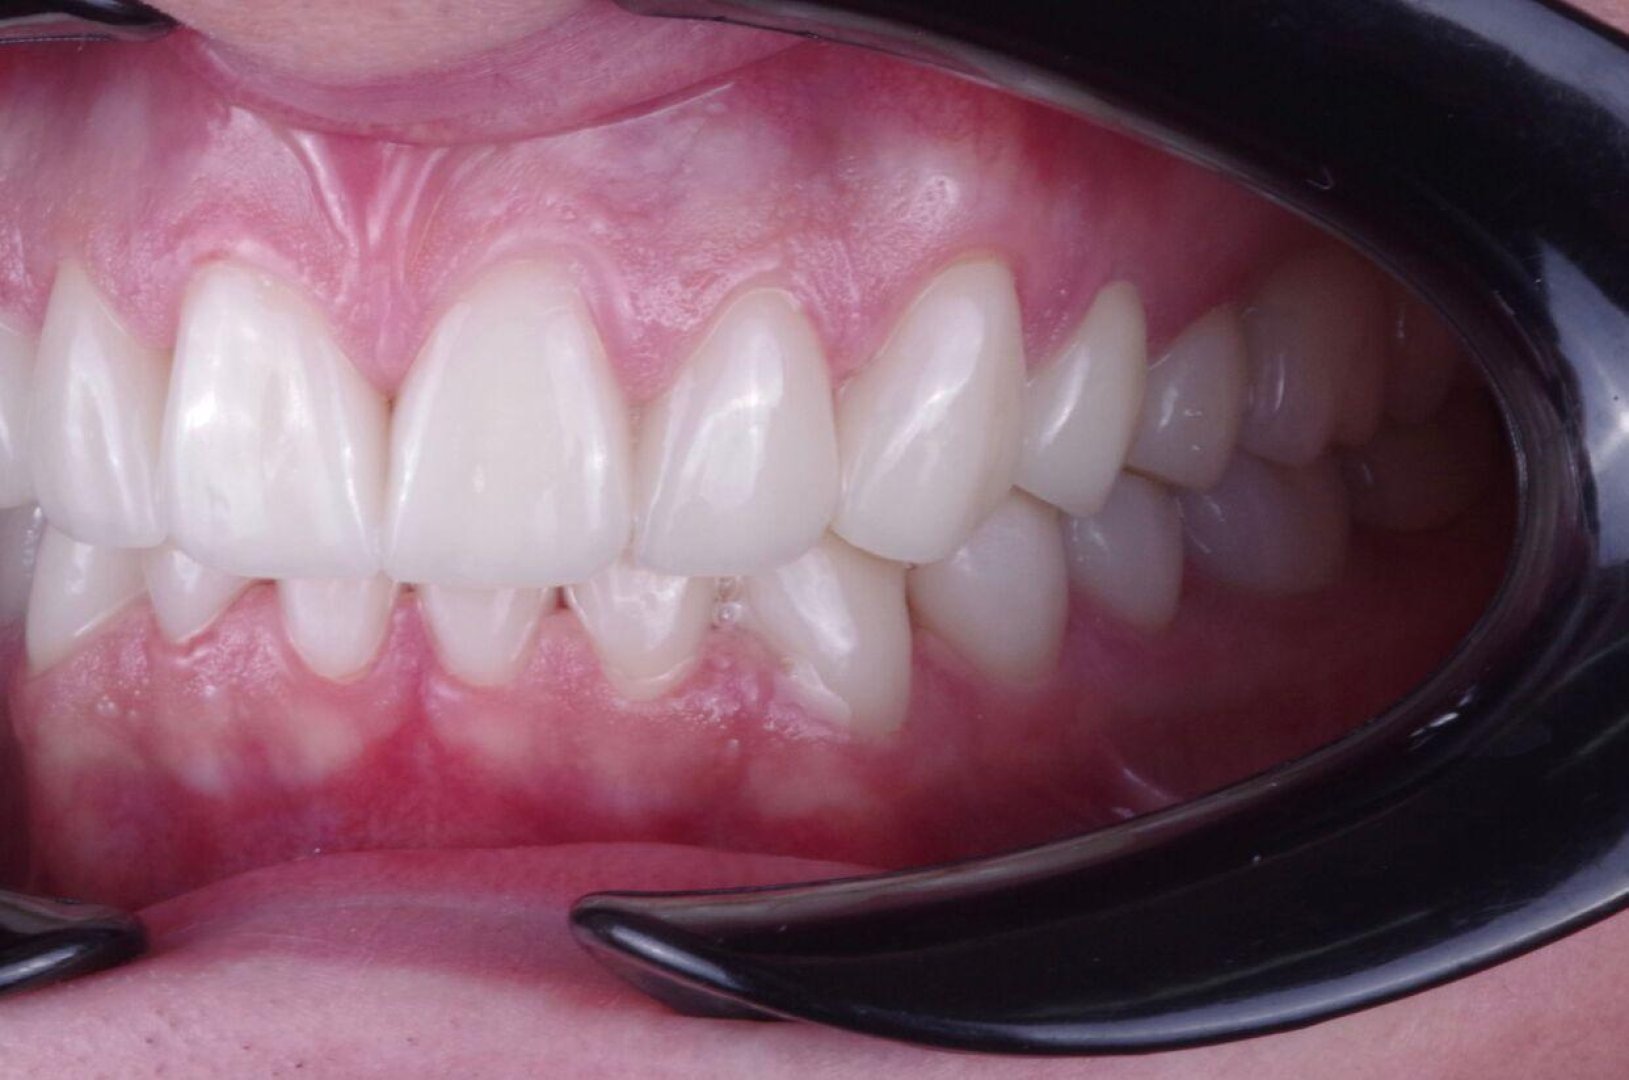

Преображение улыбки: виниры E.max (пример)

Тотальная реставрация зоны улыбки: задача — ровно, светло и при этом естественно. Обратите внимание на «живую» прозрачность и блеск — именно за это E.max любят.

ПОСЛЕ

Виниры E.max — после лечения

Как выглядит «естественно»

Важно не просто «сделать белее». Важно попасть в форму, длину, наклон и прозрачность. E.max помогает передать глубину цвета и светопреломление — поэтому виниры не выглядят плоско.